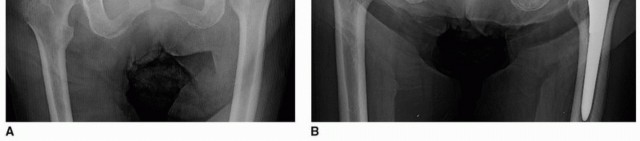

حالات استبدال مفصل الورك الأولية غير المعقدة

في غياب نقص كبير في الحُق، يفضل الأستاذ الدكتور محمد هطيف تقنية تحضير عظم الحُق التي تتضمن البرد الإنسي والمحيطي المتماثل باستخدام عدد محدود من المبارد للعمق المطلوب لتغطية الحُق. يتم اختيار مبرد الحُق الأولي بحجم يتراوح بين 3 و 5 ملم أصغر من حجم الغرسة المخطط لها (مع هدف تثبيت بضغط 1 ملم) ويتم وضعه في الاتجاه المطلوب للبرد بينما يتم البرد عرضيًا نحو القاع (الجدار الإنسي)، بدلاً من الاتجاه العلوي بشكل أساسي. يجب الاستمرار في برد الحُق حتى يتم الوصول إلى قاع الحفرة الحُقية.

يتم إجراء برد إضافي حسب الضرورة حتى يتم الحصول على تغطية كافية لمبرد الحُق. طالما بقي عظم الحُق الخلفي والجانبي كافيًا، يستمر البرد بشكل عام حتى حجم أكبر بمقدار واحد من حجم المكون المخطط له حتى يتم ملاحظة المقاومة بين المبرد النهائي والحُق الأصلي. يتم تثبيت مكون الحُق في الوضع المستهدف ويتم تقييم ثبات التركيب. إذا كان هناك ثبات كافٍ بالضغط، يمكن للجراح أن يختار ما إذا كان سيكمل التثبيت ببراغي إضافية أم لا. يفضل الأستاذ الدكتور محمد هطيف استخدام تثبيت إضافي بالبراغي في جميع عمليات إعادة بناء الحُق.